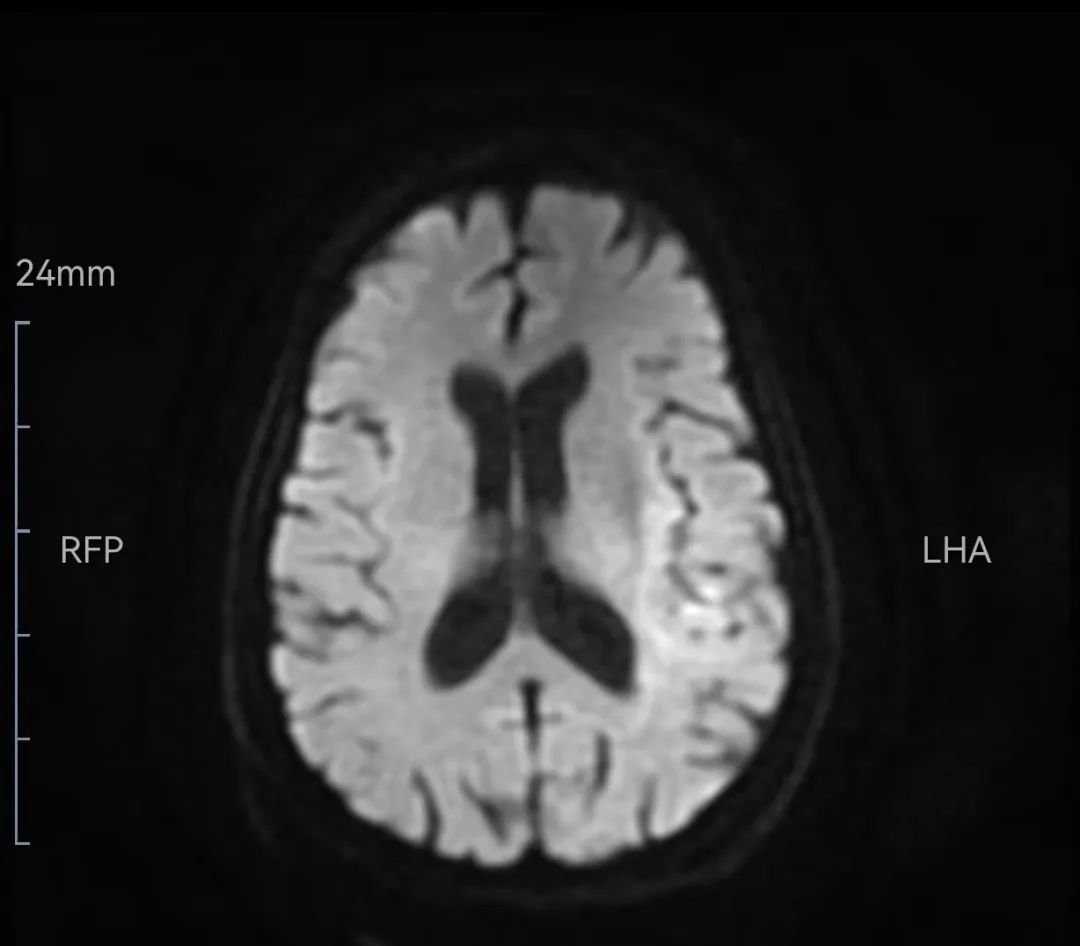

溶栓后立即检查的头颅磁共振DWI

溶栓后患者在医生及护士陪同下前往影像中心检查头颅磁共振,等候磁共振检查时再次评估,患者右侧肢体可抬离床面;NIHSS评分7分(意识2,面瘫1、右下肢运动2、感觉1、语言1),查头颅磁共振示:左侧额、顶、颞、枕叶急性脑梗塞;头颅磁共振MRA颅内大血管未见明显异常,随后收入神经内科给予进一步治疗。